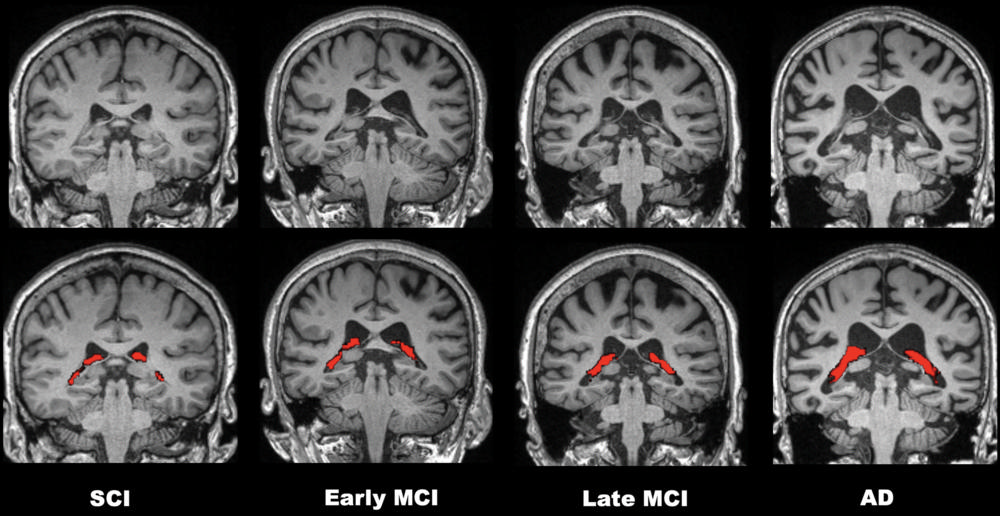

Figure 3. Comparisons of four representative 3.0-T brain MRI scans of choroid plexus (CP) volume (red) according to disease stage over the cognitive impairment spectrum. CP volume is greater in the patient with Alzheimer disease (AD) than in those with subjective cognitive impairment (SCI) or mild cognitive impairment (MCI). All patients were 75-year-old women.